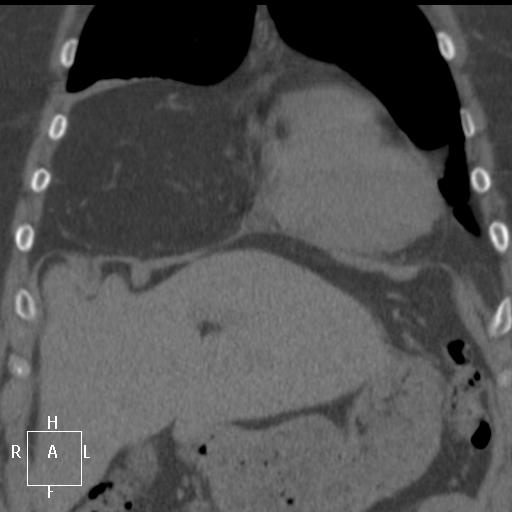

КТ. Исследование не моё, любезно предоставлено автором.

Добавлена КТ.

Новые картинки — новые проблемы

На некоторых реконструкциях не вижу я грудо-брюшной преграды. Может быть зря не вижу? А то получается, что клетчатка в впереди сердца и предбрюшинная составляют одно. Вы, Людмила Григорьевна, видите? Что-нибудь скажете?

Широкая щель (треугольник) Морганьи. Относительно тонкая и не везде видимая грудинная часть диафрагмы. В комменте 21 на аксиалах диафрагма не показана, все картинки выше неё. И еще: для только предбрюшинной клетчатки - её слишком много, скорее тут сальник в грудную полость пролабирует.

Грыжа Морганьи с пролабированием сальникового жира в плевральную полость.